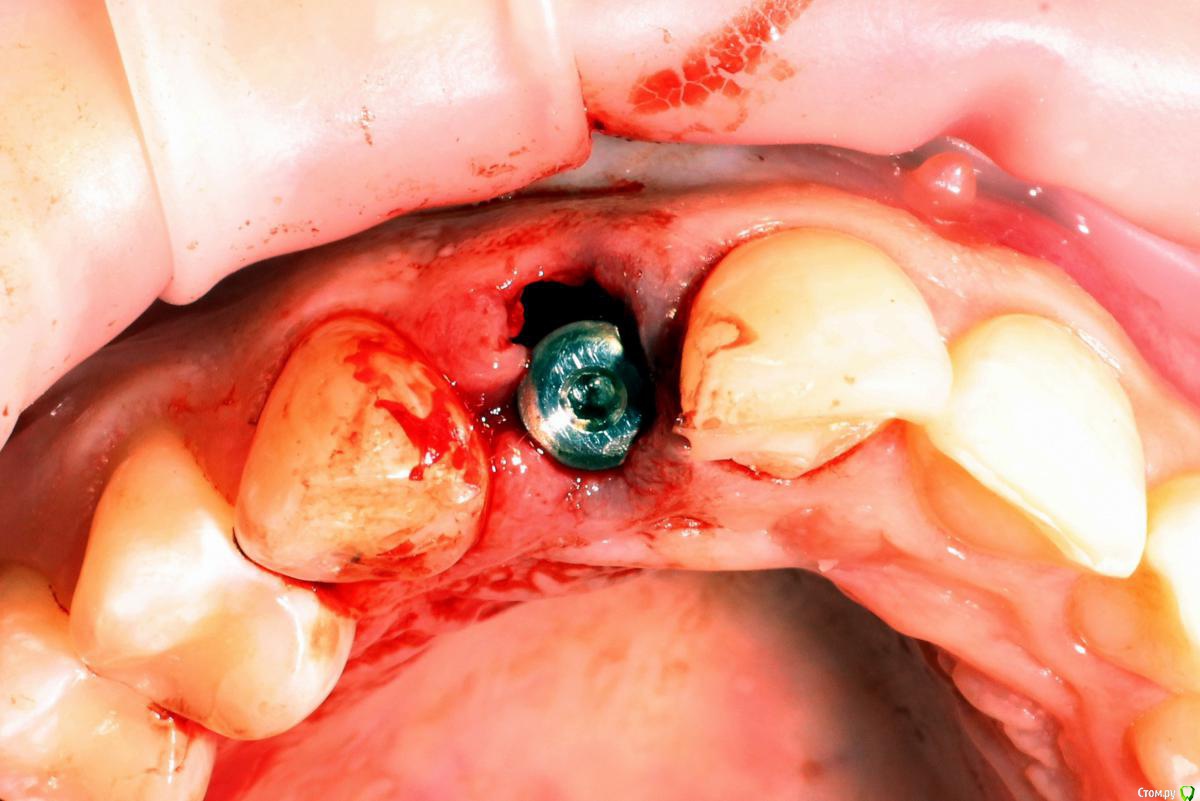

MenshikovDV Опубликовано 2 апреля, 2015 Поделиться Опубликовано 2 апреля, 2015 (изменено) Зуб 1.2 отлом коронковой части зуба, на период ожидания приема у хирурга и ортопеда (2 дня) приклеен к соседям. Вся процедура в одно посещение. Где-то часа два. Я ортопед, хирургия не моя, фото мои Изменено 2 апреля, 2015 пользователем MenshikovDV 19 Ссылка на комментарий

АнтонТЛТ Опубликовано 4 апреля, 2015 Поделиться Опубликовано 4 апреля, 2015 Судя по фото Alpha bio SPI, торк около 40 Ссылка на комментарий

MenshikovDV Опубликовано 5 апреля, 2015 Автор Поделиться Опубликовано 5 апреля, 2015 торк намного больше 40 Ссылка на комментарий

Aquarius Опубликовано 5 апреля, 2015 Поделиться Опубликовано 5 апреля, 2015 в такую дыру лучше что-нибудь кинуть, имхо. Ссылка на комментарий

Alexey Doc Опубликовано 5 апреля, 2015 Поделиться Опубликовано 5 апреля, 2015 Класс! Аккуратно сработали!Единственно, думаю что аугментации была бы желательна. Ссылка на комментарий

Brigita Опубликовано 5 апреля, 2015 Поделиться Опубликовано 5 апреля, 2015 на удаленном зубе какая то железячка хвостиком торчит))) Ссылка на комментарий

MenshikovDV Опубликовано 7 апреля, 2015 Автор Поделиться Опубликовано 7 апреля, 2015 ИНСТРУМЕНТ сломан в канале )) Ссылка на комментарий